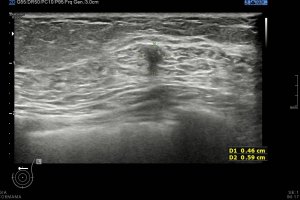

Los vientres anteriores de los músculos Digástricos, que son el objeto del desarrollo de este Post, son dos estructuras musculares redondeadas en el corte transversal, imagen 1, y alargados si los estudiamos en el eje largo, imagen 3, mira:

Ecográficamente los músculos digástricos en eje corto tienen semiología hipoecogénica, en aspecto de noche estrellada, como la de hoy, y en el eje largo en forma de penacho o en forma de plumas con las fibras alargadas y paralelas a la superficie.

Acostúmbrate a mirar esta anatomía en los estudios de cuello sobre todo en pacientes infantiles, por posible localización de adenopatías. En la edad adulta pueden objetivarse cambios de grosor, infrecuentemente, en esta musculatura por diferentes motivos.